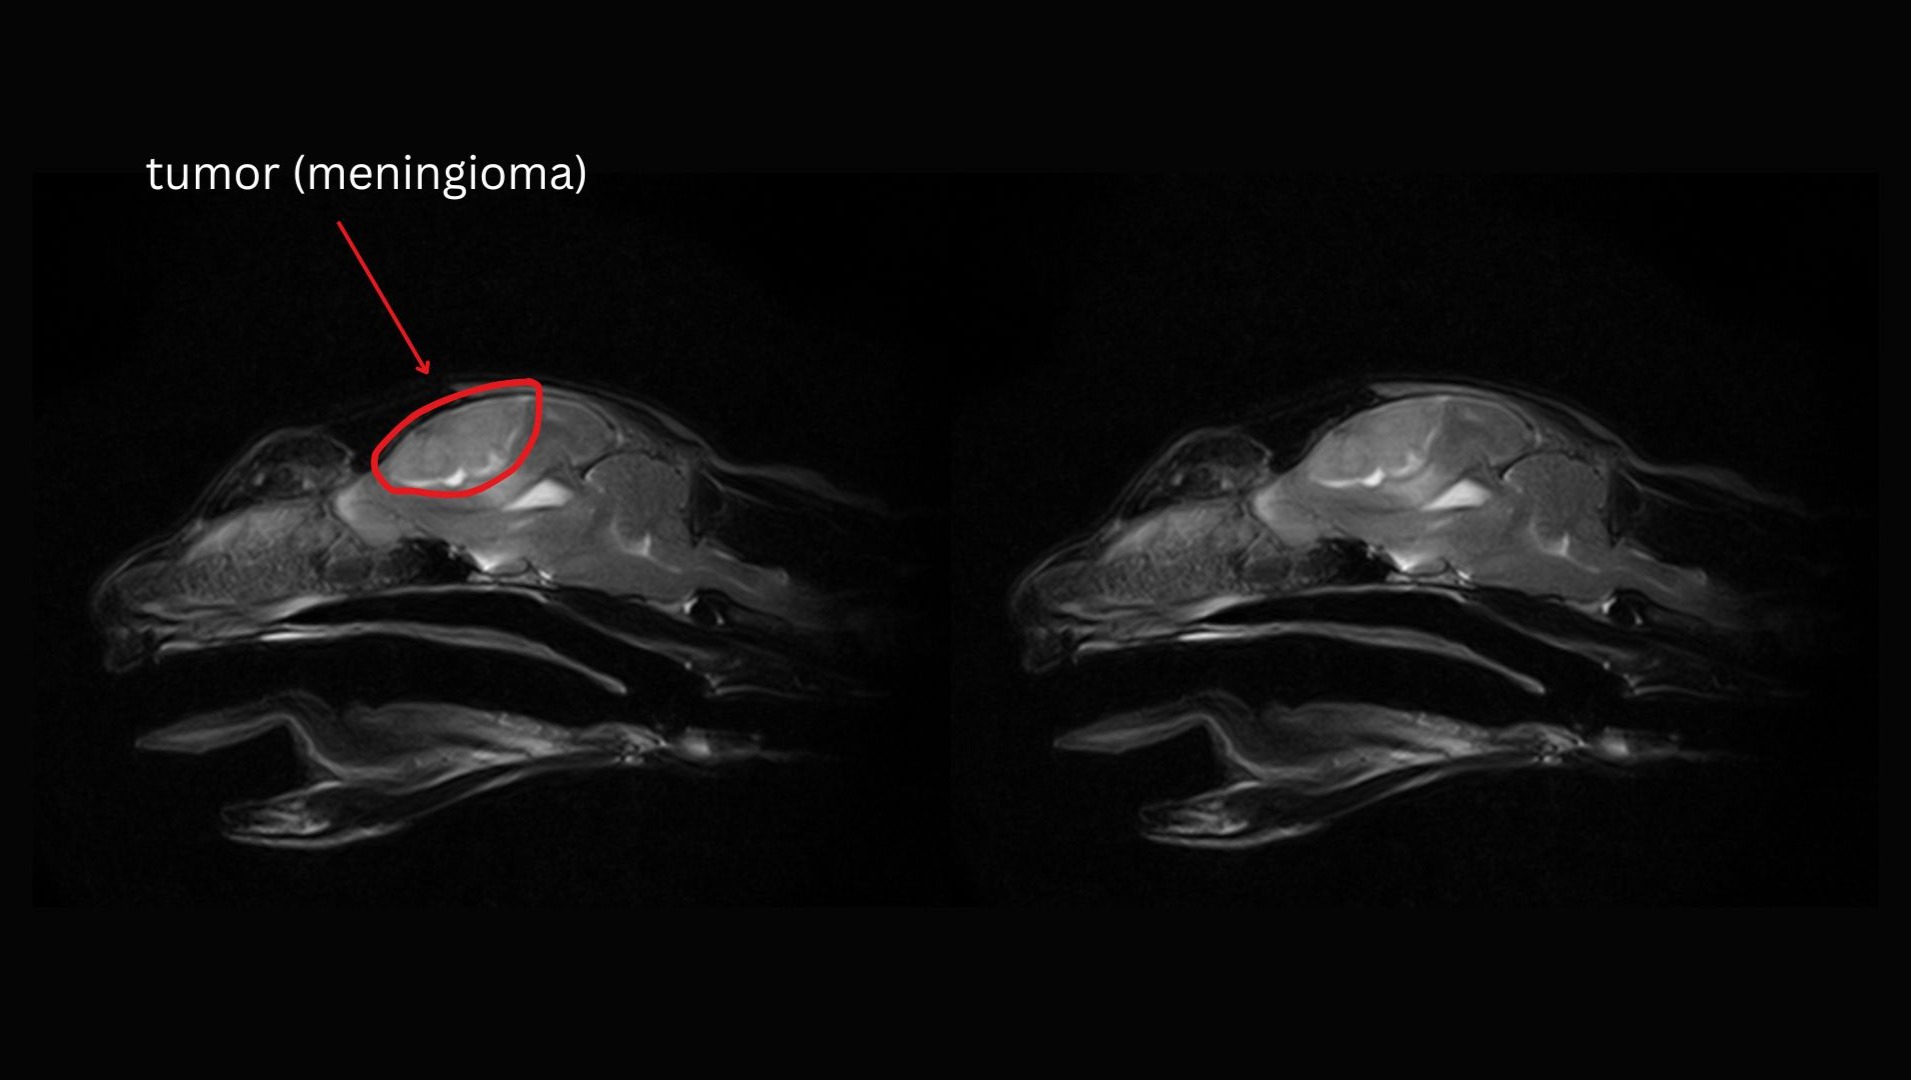

On October 30, we took Wendy to Remedy, where she underwent anesthesia and an MRI scan, which revealed a large meningioma that was putting immense pressure on her brain. Dr. Mona Qahwash, the neurologist, expressed her concern that, without surgery, "Wendy could pass away at any moment", as the tumor could begin to interfere with vital reflexes, including her ability to breathe.

Wendy's MRI's: